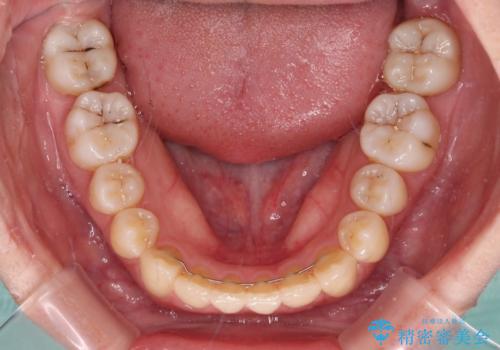

非常にしっかりとマウスピースを装着してくださいましたが、前歯の排列がなかなか仕上がらずに期間がかかってしまいました。